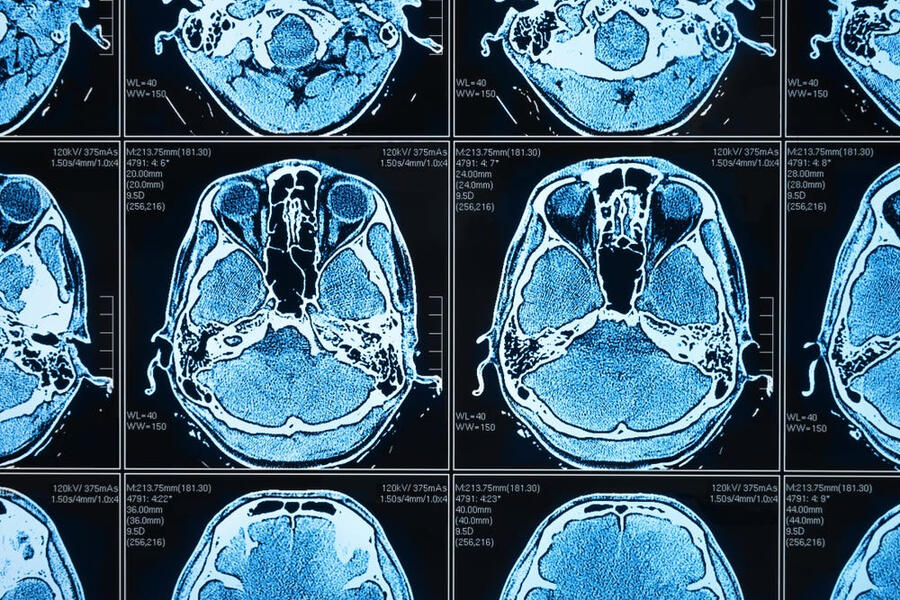

Using Neural Networks to Predict Brain Tumors

Objective: Build a machine learning model to classify brain tumors using MRI scans.

Data Preprocessing: Applied techniques like image resizing and normalization to prepare MRI data for modeling.

Modeling: Utilized convolutional neural networks (CNNs) with TensorFlow and Keras for training.

Results: The model achieved high classification accuracy, indicating its effectiveness in distinguishing between tumor types from MRI images.